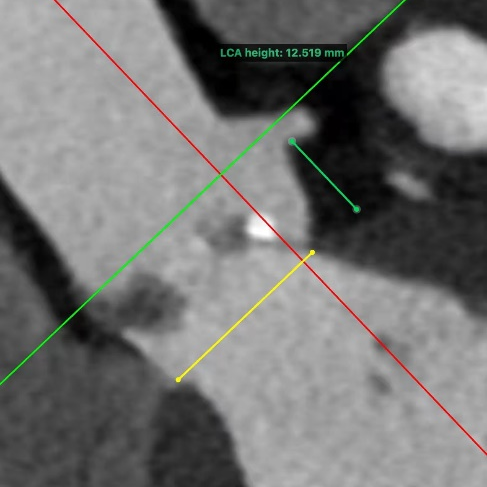

术前CT

瓣环:周长71.9mm,最大径25.6mm

法氏窦:周长109.7mm,最大径36.0mm

STJ:周长86.2mm

左冠高度:12.519mm

右冠高度:20.306mm